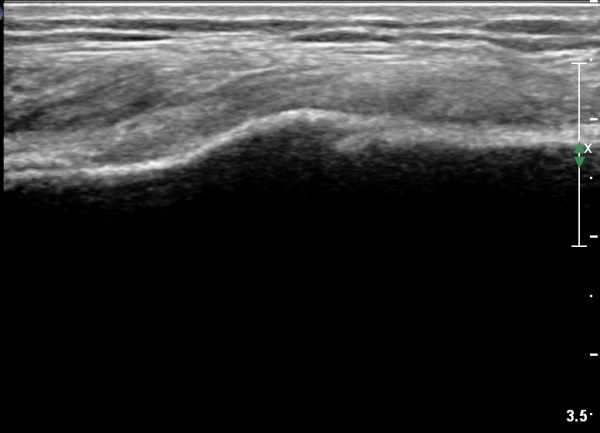

[¹«¸­] °æ°ñ ÇǷΰñÀý ÃÊÀ½ÆÄ¼Ò°ß(sonographic findings of stress fracture of tibia)

¿ìÃø ¹ß¸ñ°ú ¾Æ·§´Ù¸® ÅëÁõ(±â°£ 2ÁÖ)

±º´ë¿¡ ÀÔ´ëÇÏ¿© ÈÆ·ÃÀ» ¹ÞÀº º´·ÂÀÌ Àִ ȯÀÚ´Â ¾à 2ÁÖ ÀüºÎÅÍ ¹ß¸ñ ºÎÀ§ÀÇ ÅëÁõÀÌ ÀÖ´ø Áß

ÃÖ±Ù¿¡´Â ¹ß¸ñ À§ ¾Æ·§´Ù¸®¿¡ ÅëÁõÀÌ ¹ß»ýÇÏ°í ½ÉÇÏ°Ô °ÉÀ¸¸é ½ÉÇØÁö´Â ¾ç»óÀÓ

¾Æ·§´Ù¸® Áß°£ ºÎÀ§¿¡ °æ¹ÌÇÑ ¿¬ºÎÁ¶Á÷ ºÎÁ¾ÀÌ °üÂûµÇ°í ¾à°£ÀÇ ±¹¼ÒÀû ¾ÐÅëÀ» º¸ÀÓ.

ÃÊÀ½ÆÄ °Ë»ç

¹Ì¼¼ÇÏ°Ô ¿¬ºÎÁ¶Á÷ ºÎÁ¾°ú °¡°ñ Çü¼ºÀÌ °üÂûµÊ.